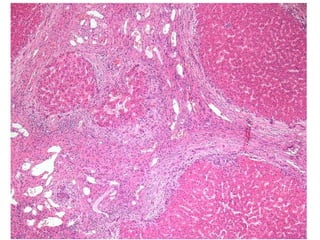

LS08-10290 Abnormal LFT, negative for Hepatitis A, B, C.  Sono: heterogeneous liver.

BS09-10453:  Dx: Chronic hepatitis, with severe activity (focal parenchymal collapse) and cirrhosis, suggestive of autoimmune hepatitis. Corresponds to: Modified Ishak stage 4/4 Metavir F4

LS08-10290 Abnormal LFT,negative for Hepatitis A, B, C. Sono: heterogeneous liver.

BS09-10453: Dx:Chronic hepatitis, with severe activity (focal parenchymal collapse) and cirrhosis, suggestive of autoimmune hepatitis. Corresponds to: Modified Ishak stage 4/4 Metavir F4